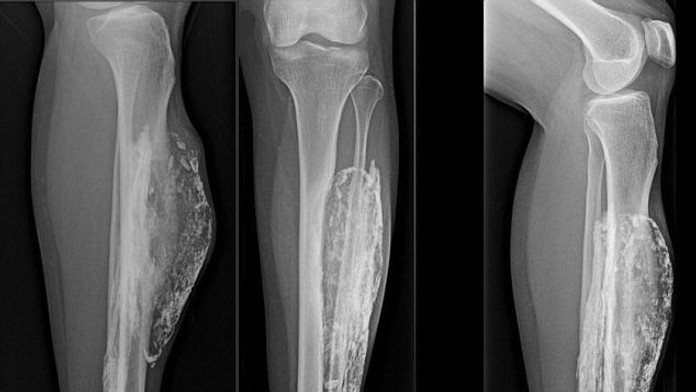

Noha pohrýzenej Thajčanky

Zdroj: dailymail.co.uk

Dnes jej diagnostikovali kompartment syndróm.

Ženu z Thajska pohrýzol had, keď mala 14 rokov. Malajská vretenica ju do nohy uhryzla tak silno, že jej prerazila kožu. Myslela si, že to nič nie je. Avšak pred desiatimi rokmi zistila, že ju noha bolí a niečo jej tam rastie. Thajčanka má teraz 66 rokov a viac ako 50 rokov jej v nohe vyrastala obrovská hmota.

Lekári jej spravili röntgen a diagnostikovali kompartment syndróm. Ochorenie nie je nič nezvyčajné, avšak u ženy rástol neuveriteľných 52 rokov. Tento syndróm je stav, pri ktorom zvýšený tkanivový tlak v uzavretom priestore spôsobuje poruchu cirkulácie a poškodenie svalov, nervov a ostatných zložiek. Aj keď s komplikáciami, hmotu jej chirurgicky odstránili.